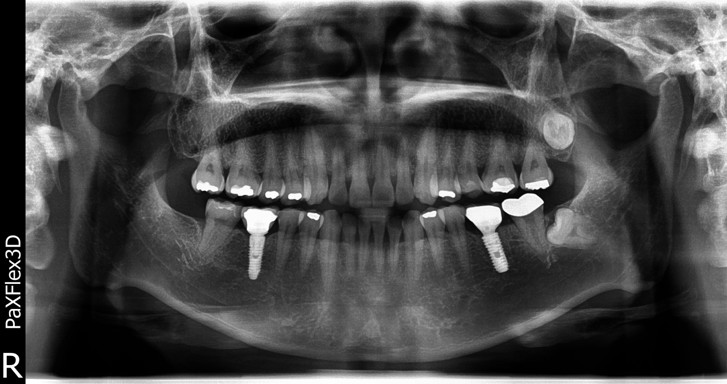

엑스레이 촬영 결과,

치아 머리 부분뿐 아니라

잇몸 아래 뿌리까지

금이 깊게 내려간 상태였습니다.

엑스레이 상에서 확인해보았을때도

상당히 안정적인 모습입니다 ^^